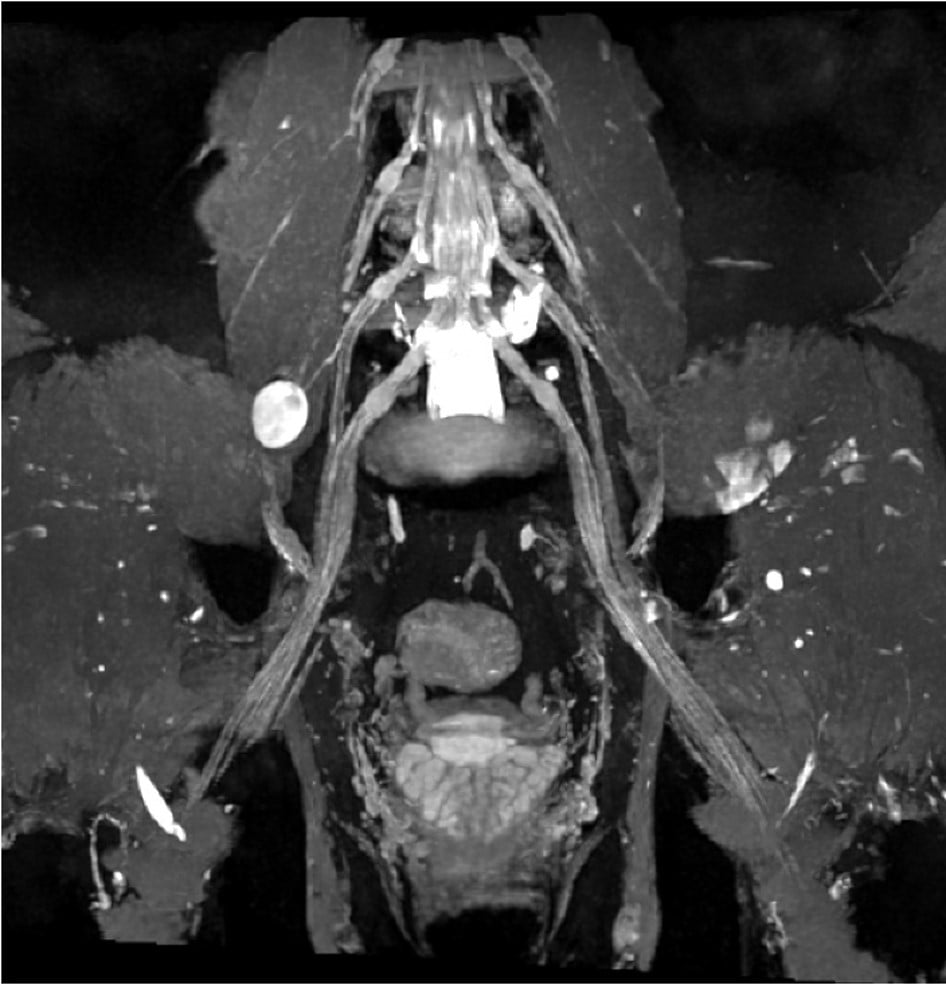

3D MR Neurography (MRN): Peripheral Neve Sheath Tumor Arising from Right Femoral Nerve of Lumbosacral Plexus (Pelvis)

Magnetic Resonance Neurography (MRN)

MRN uses high-resolution magnetic resonance imaging (MRI) to depict and interrogate peripheral nerves that are difficult to capture with conventional MRI. Characterization of peripheral nerve injury aids in the diagnosis and management of traumatic and atraumatic conditions.